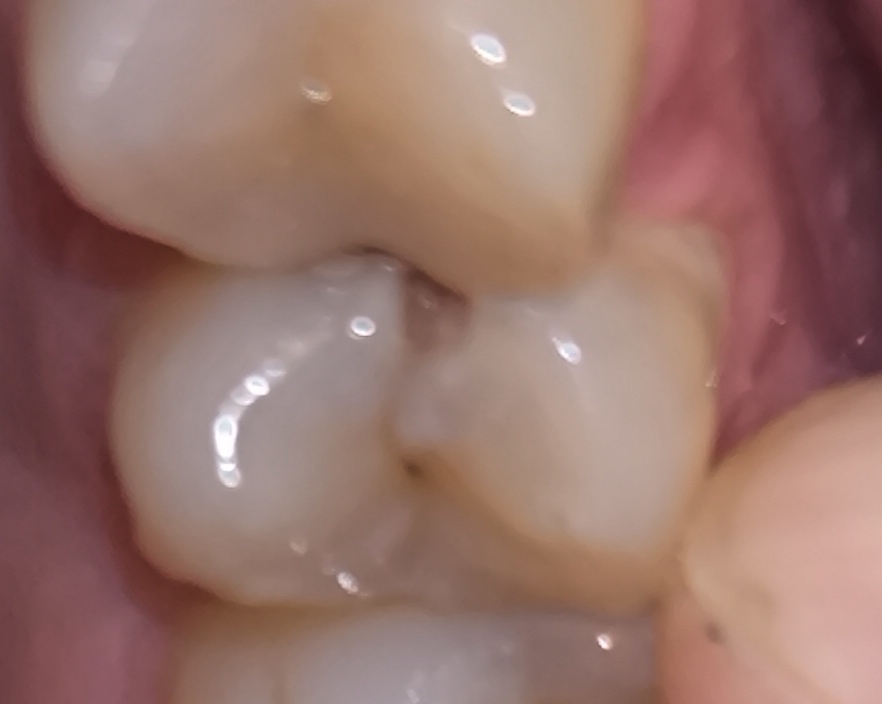

Аноним 07/08/25 Чтв 13:36:06 #27 №1635134

>>1634947

>Как профиль лица меняется после удаления восьмерок

Удаляли две, одну сверху другую снизу. Никаких изменений.

Но если у тебя они кривые и растут вбок например то конечно станет лучше

>>1633720